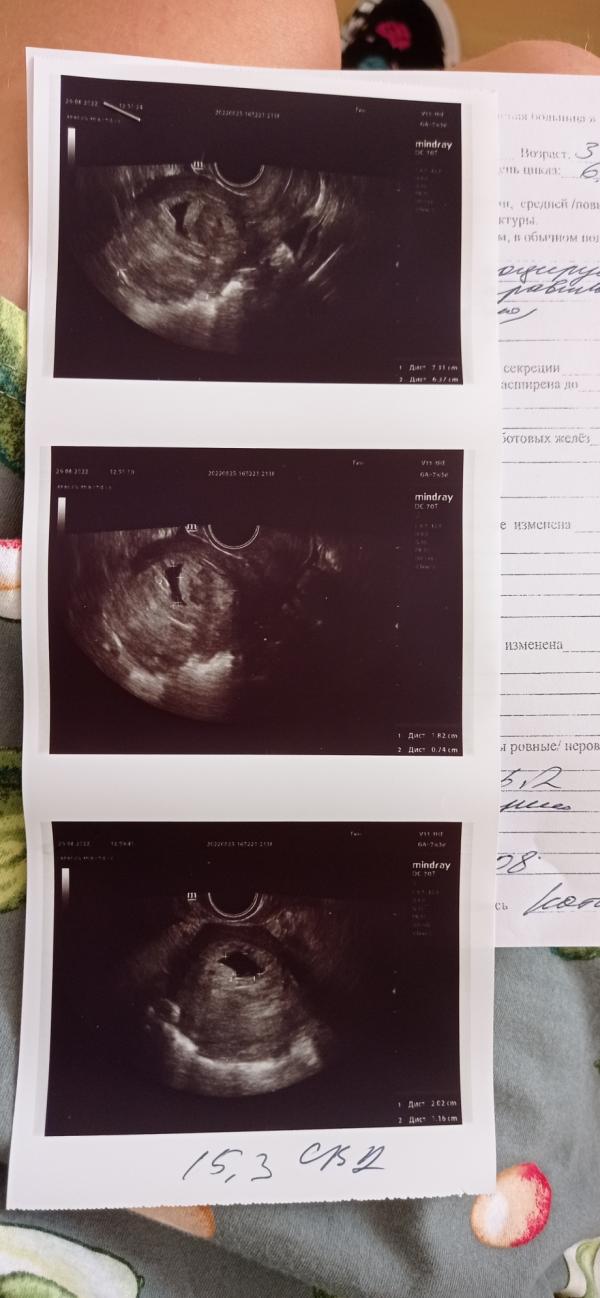

Девочки, может было у кого. После криопереноса, на 5,1 нед ещё на узи было все хорошо, показыаало плодное яйцо, желточный мешочек, так как срок маленький, сказали эмбрион позже появится. В 5.5 нед. пошло кровотечение, отвезли в больницу, на УЗИ показало деформация плодного яйца, через три дня на узи улучшений не было, деформация существует, эмбриона все также не видно, на УЗИ не спросила про желточный мешочек, и не написали ничего. Контрольное узи на 31.08, будет 7 недель. Мысли уже всякие, либо идет регресс, то будут чистить, я откажусь. Конечно хочется верить в лучшее. Может были у кого случаи, чем закончилось, готова выслушать и плохое и хорошее.

В 6 недель делала узи, было только плодное яйцо и желточный мешочек, сказали прийти через неделю, полторы, но в 6.5 недель закровила попала на сохранение, в 7 недель сделали узи уже билось сердечко.